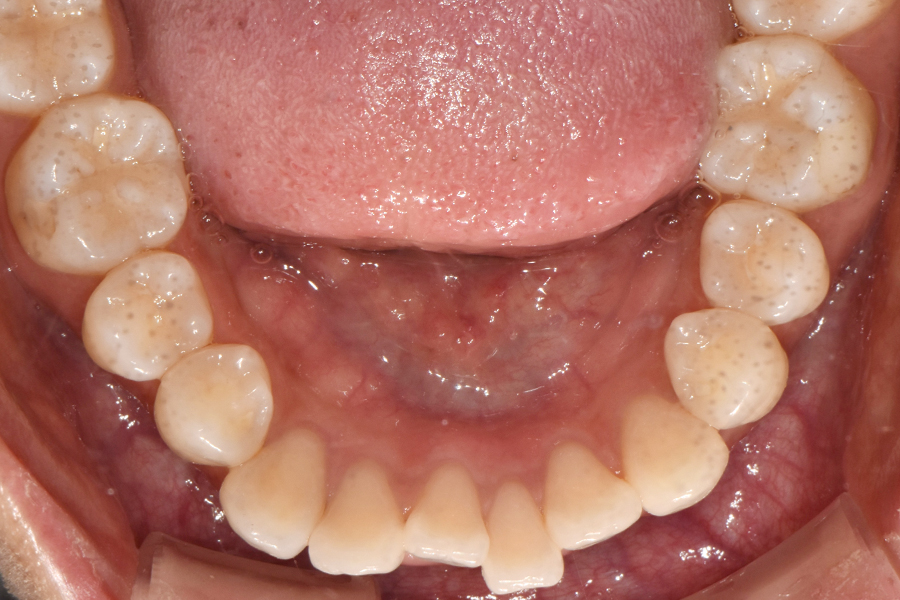

윗니를 보시면 치아 위치가 많이 틀어진 것을 볼 수 있는데요. 아래쪽 같은 경우 비교적 윗니보다 낫지만 그래도 한 쪽 치아가 좀 많이 튀어나와 있고 전체적인 악궁 형태가 조금 찌그러져 있는 것을 볼 수 있습니다.